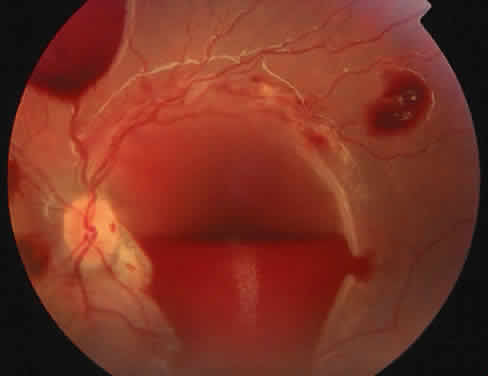

The most common ocular manifestations of TTP include papilledema, extraocular muscle palsies, and visual field defects, which usually are secondary to concomitant CNS involvement.75 Retinal findings consist of hemorrhages, retinal vascular occlusions, and serous detachments76,77 (Figs. 8 to 10). The cause of the serous detachments appears to be focal occlusion of the choriocapillaris resulting in retinal pigment epithelial damage and blood-retinal barrier disruption.76,77 Findings on fluorescein angiography are characterized by focal areas of nonperfusion of the choriocapillaris associated with late leakage into the subretinal space76 (Fig. 11). This is consistent with histopathologic studies that show occlusion of the choriocapillaris and large choroidal vessels, presumably by fibrin, with overlying necrosis of thepigment epithelium.75,76 TTP also has been linked in one case report with Purtscher retinopathy.78

Fig. 8. Patient with thrombotic thrombocytopenic purpura and extensive retinal vascular-occlusive disease. (Courtesy of William Mieler, MD.)

Fig. 10. A 42-year-old woman with thrombotic thrombocytopenic purpura and neurosensory retinal detachments. (Courtesy of Jerry Neuwirth, MD.)

Clinically, the development of serous retinal detachments usually is associated with exacerbations of TTP and the development of acute hypertension. Although serous retinal detachments have been described as a preterminal event, resolution of the detachments with subsequent pigment epithelial changes may occur when the underlying hypertension and thrombocytopenia are controlled.77